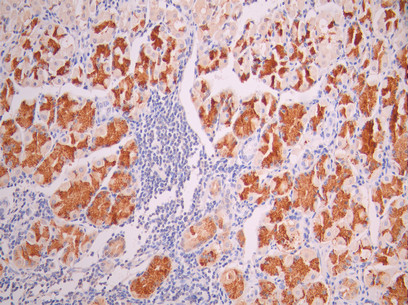

在胰腺导管腺癌(PDAC)中,MUC1被识别为蛋白互作网络核心基因之一 [22]。组织病理学研究显示,其在癌组织中的表达显著高于正常导管组织 [25]。基于胰液DNA甲基化的检测方法可在较高特异性与灵敏度下区分PDAC与IPMN [23],显示出其在早期鉴别诊断中的潜在应用价值。值得注意的是,MUC1不仅是诊断标志物,其胞质尾区通过持续激活PI3K/Akt信号维持肿瘤细胞生存优势,提示其在治疗靶向中的重要地位。

[25] Alberto Nicoletti, Federica Vitale, Giuseppe Quero, Mattia Paratore, Claudio Fiorillo, Marcantonio Negri, Angela Carlino, Frediano Inzani, Antonio Gasbarrini, Sergio Alfieri, Lorenzo Zileri Dal Verme.(2023). Immunohistochemical Evaluation of the Expression of Specific Membrane Antigens in Patients with Pancreatic Ductal Adenocarcinoma.